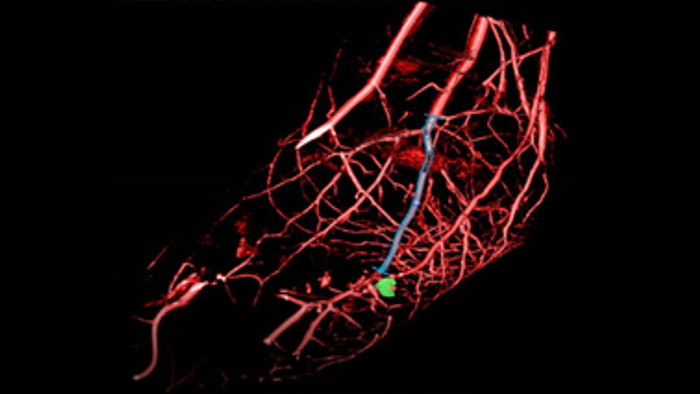

SmartCT Vaso proporciona imágenes 3D de alta resolución que revelan información clave sobre las estructuras vasculares cerebrales para apoyar la mayor evaluación espacial posible del contexto de los vasos.

SmartCT Roadmap facilita intervenciones complejas porque proporciona una guía de imágenes en 3D en directo que puede segmentarse para resaltar el vaso y las lesiones objetivo, con lo que ayuda a la navegación a través de estructuras vasculares complejas. Todo ello controlado a través de la pantalla táctil de la mesa.